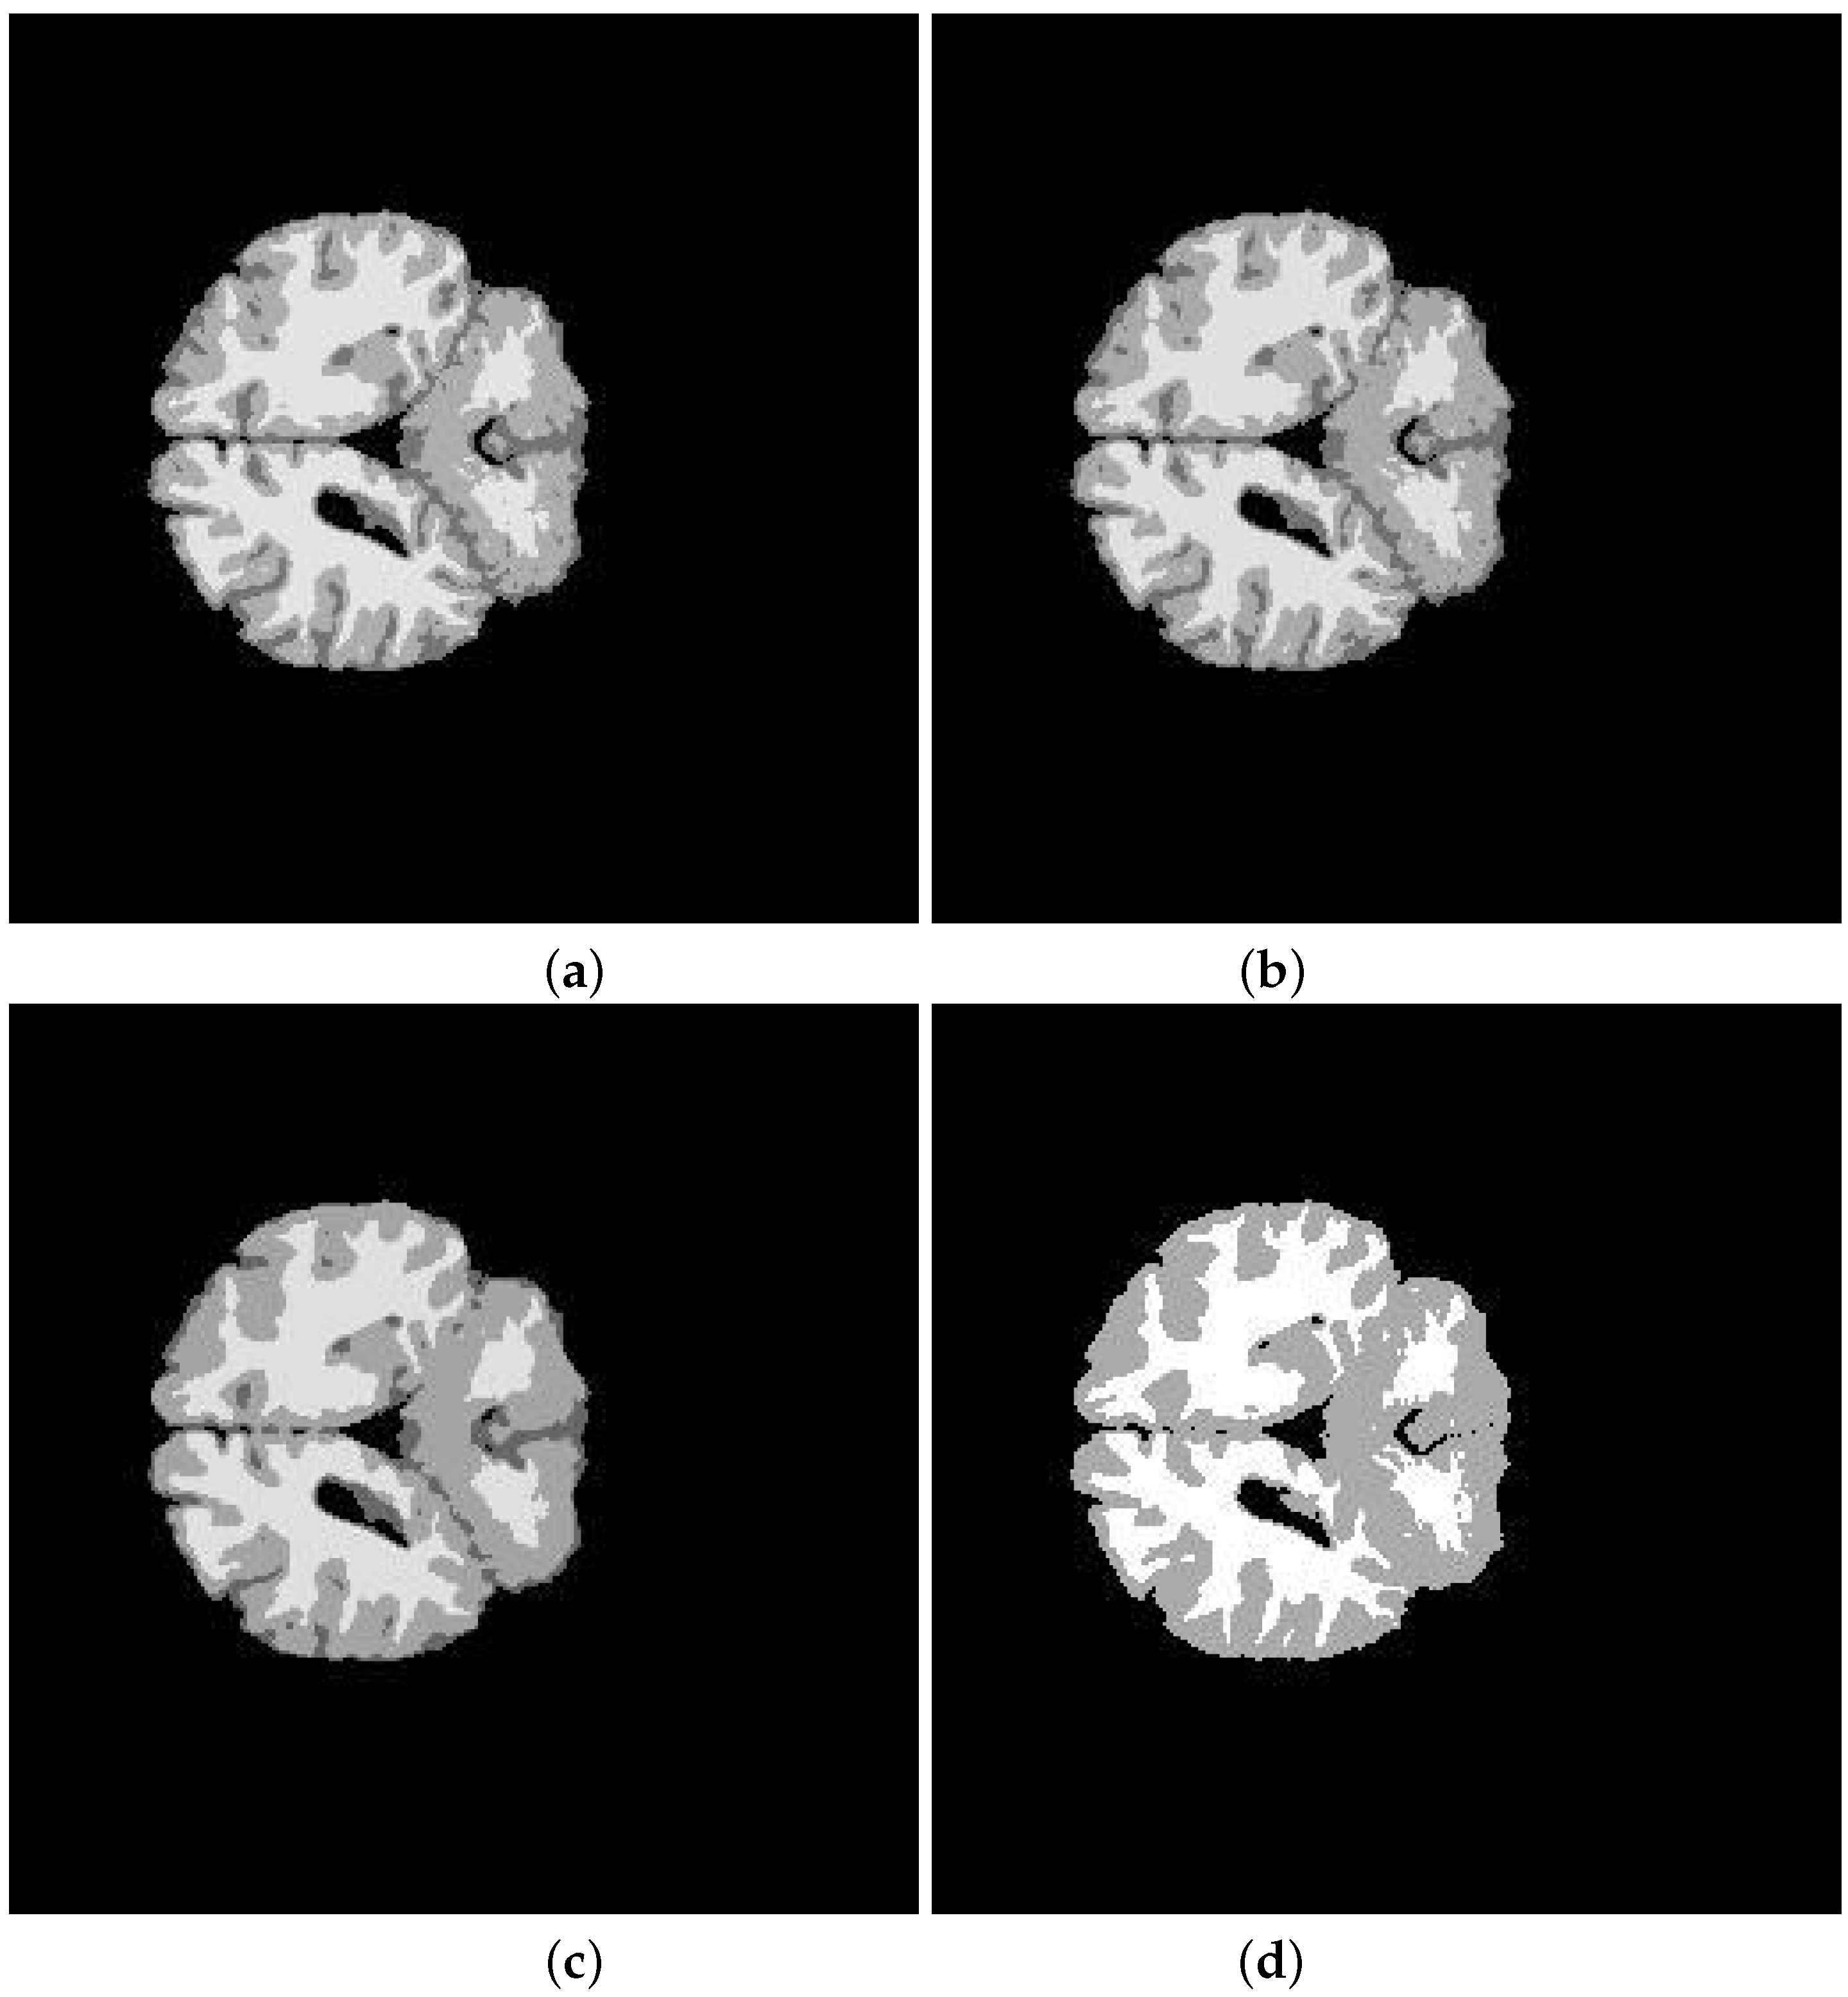

| Subject | Method | JS | DSC | Sensitivity | Specificity | Accuracy |

|---|---|---|---|---|---|---|

| K-means | % | |||||

| 202-3 | ||||||

| 0.8938 | 0.9486 | |||||

| K-means | ||||||

| 205-3 | ||||||

| Segmented Image | K-means | FCM | SFCM | KFCM |

|---|---|---|---|---|

| 202-3 original | 0.5842 | 0.5850 | 0.5832 | 0.5889 |